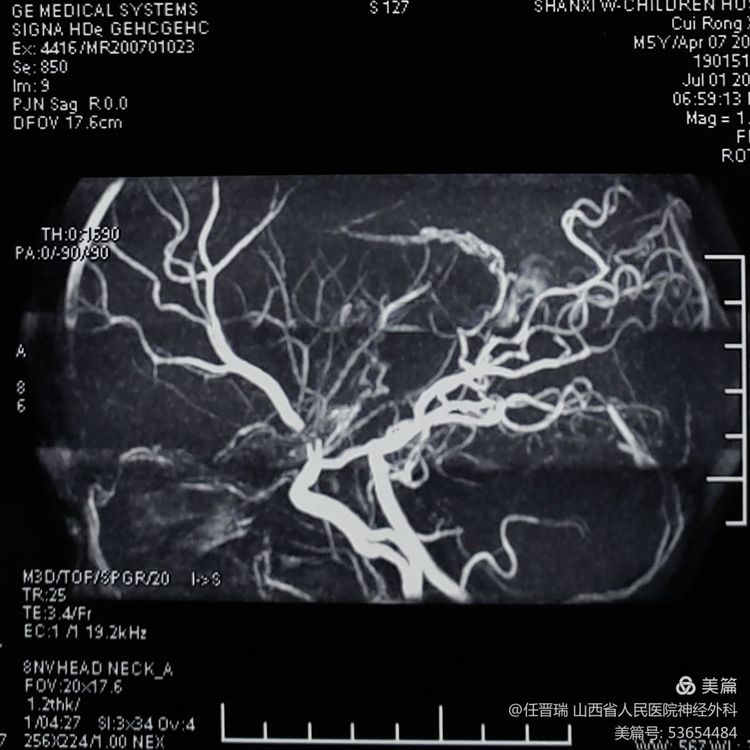

入院3月前颅脑MR: 双侧额顶叶可见多发急性脑梗死灶

3月前颅脑MRA:双侧大脑中动脉闭塞及双侧大脑前动脉闭塞

全脑血管造影:双侧大脑中动脉及双侧大脑前动脉闭塞,颈内动脉末端烟雾样血管形成